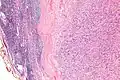

| Micrograph of an intranodal palisaded myofibroblastoma. H&E stain. | |

IPMs are diagnosed by examination of the tissue by a pathologist. They have a rim of peripheral lymphoid tissue (remnant of a lymph node) and consist of spindle cells with nuclear palisading. Red blood cell extravasation is common and blood vessels surrounded by collagen with (fine) peripheral spokes (amianthoid fibers) are usually seen.[2]

Immunostains for smooth muscle actin and cyclin D1 are characteristically positive. The main histologic differential diagnosis is schwannoma.

High mag.